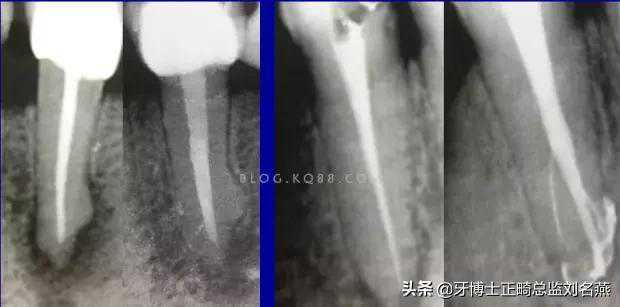

5、预备到多少号结束

根管预备理想的情况应该预备到多大锥度,多少号,预备后根管空间是金字塔还是埃菲尔铁塔。专家经过离体牙根尖切片研究发现根尖狭窄部远比想象的要大,如果根管预备太小就会残留感染物,根管的部分空间就不会预备到,残留的感染物就会造成治疗效果达不到预期目标。只有做到了充分的预备,尽可能地多冲洗才会有好的结果。

根管治疗要做到看清楚,去干净,充恰满,封严密,就会达到期望的结果。2200年前的病例只充填了冠1/3可以理解、可以接受;2200年后的今天我们有先进的设备和材料,就要充填出大锥度高密度的完美结果。理念决定技术,标准决定技术的提高和进步。